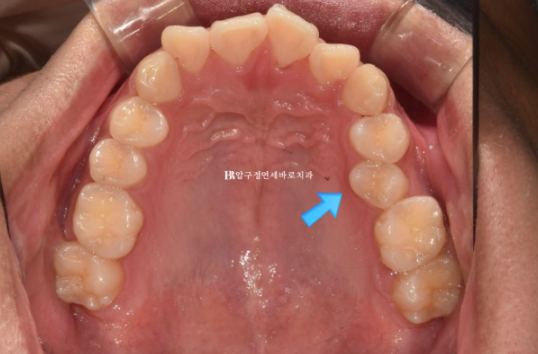

23.12

교합면 사진에서 보듯 치아가 입천장으로 들어가 있기 때문입니다.

이렇게 배열에서 벗어나게 나온 영구치를 이소맹출된 치아 라고 합니다.

24.06

배열도 가지런해졌고 이소맹출이 되어서 입천장으로 들어가있던 치아도 제자리를 찾았습니다.

이 부분 해결을 위해 고무줄 처방이 있었습니다.

사진상 금속 고리끼리 고무줄을 겁니다.